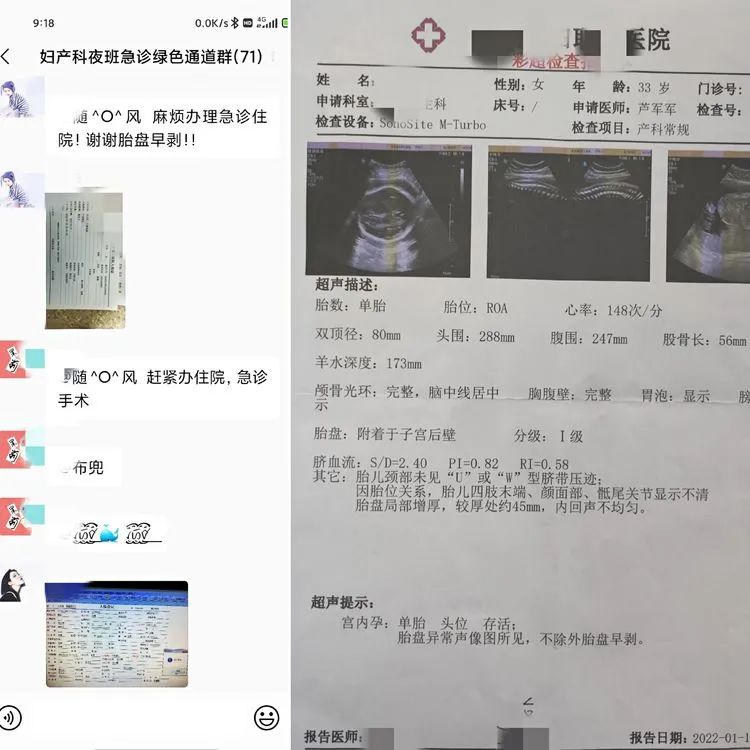

西安医学院第二附属医院对患者造成误诊

图片尺寸1279x1707

阴道异常流血伴腹痛,竟然是宫外孕?_周口_输卵管_陈女士

图片尺寸1080x720

女子称b超未查出怀孕被开禁服药导致打胎,金华妇幼保健院:正协商|金华

图片尺寸640x699